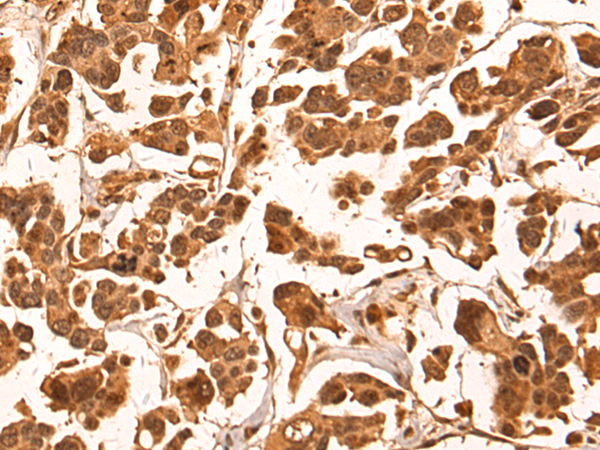

分类: 科研抗体货号: P10585别名: GRP3应用: WB,IHC反应种属: Human